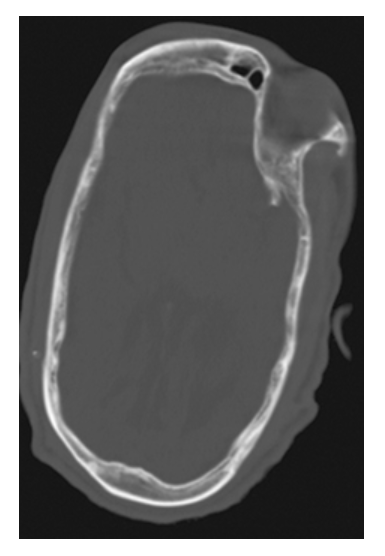

Crainosynostosis. Axial NECT shows elongation of the calvarium in the antero-posterior dimension and narrowing in the transverse dimension.

Crainosynostosis. Coronal NECT shows premature complete fusion of the sagittal suture.